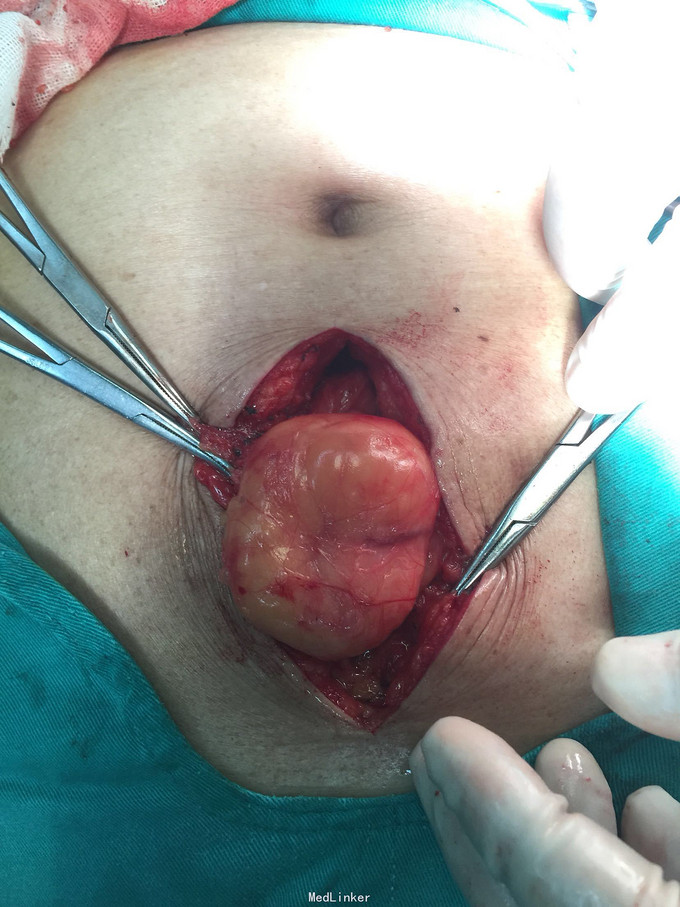

上腹部正中可复性包块10年不可还纳伴疼痛5小时

上腹壁见大小约5cm直径包块,压痛,质硬。

上腹部白线疝嵌顿,肠粘连,小肠嵌顿。肺炎。冠心病。白线缺损直径约4cm,急诊手术行上腹部白线疝嵌顿松解,小肠松解粘连,部分小肠还纳,白线疝补片修补术。

术后5天出院,出院1月复诊良好,未诉特殊不适。白线疝发病较少,嵌顿更少,小的可直接缝合腹直肌层,大的补片修补。疝病应及时治疗,老年高龄多发病急诊手术有点烦。